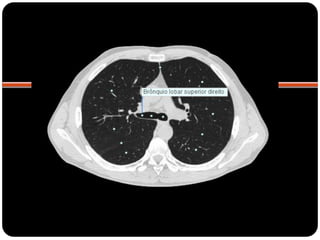

BPD: BLSD

BI - BLM

BI – BLID

BPE: BLSE

BLIE